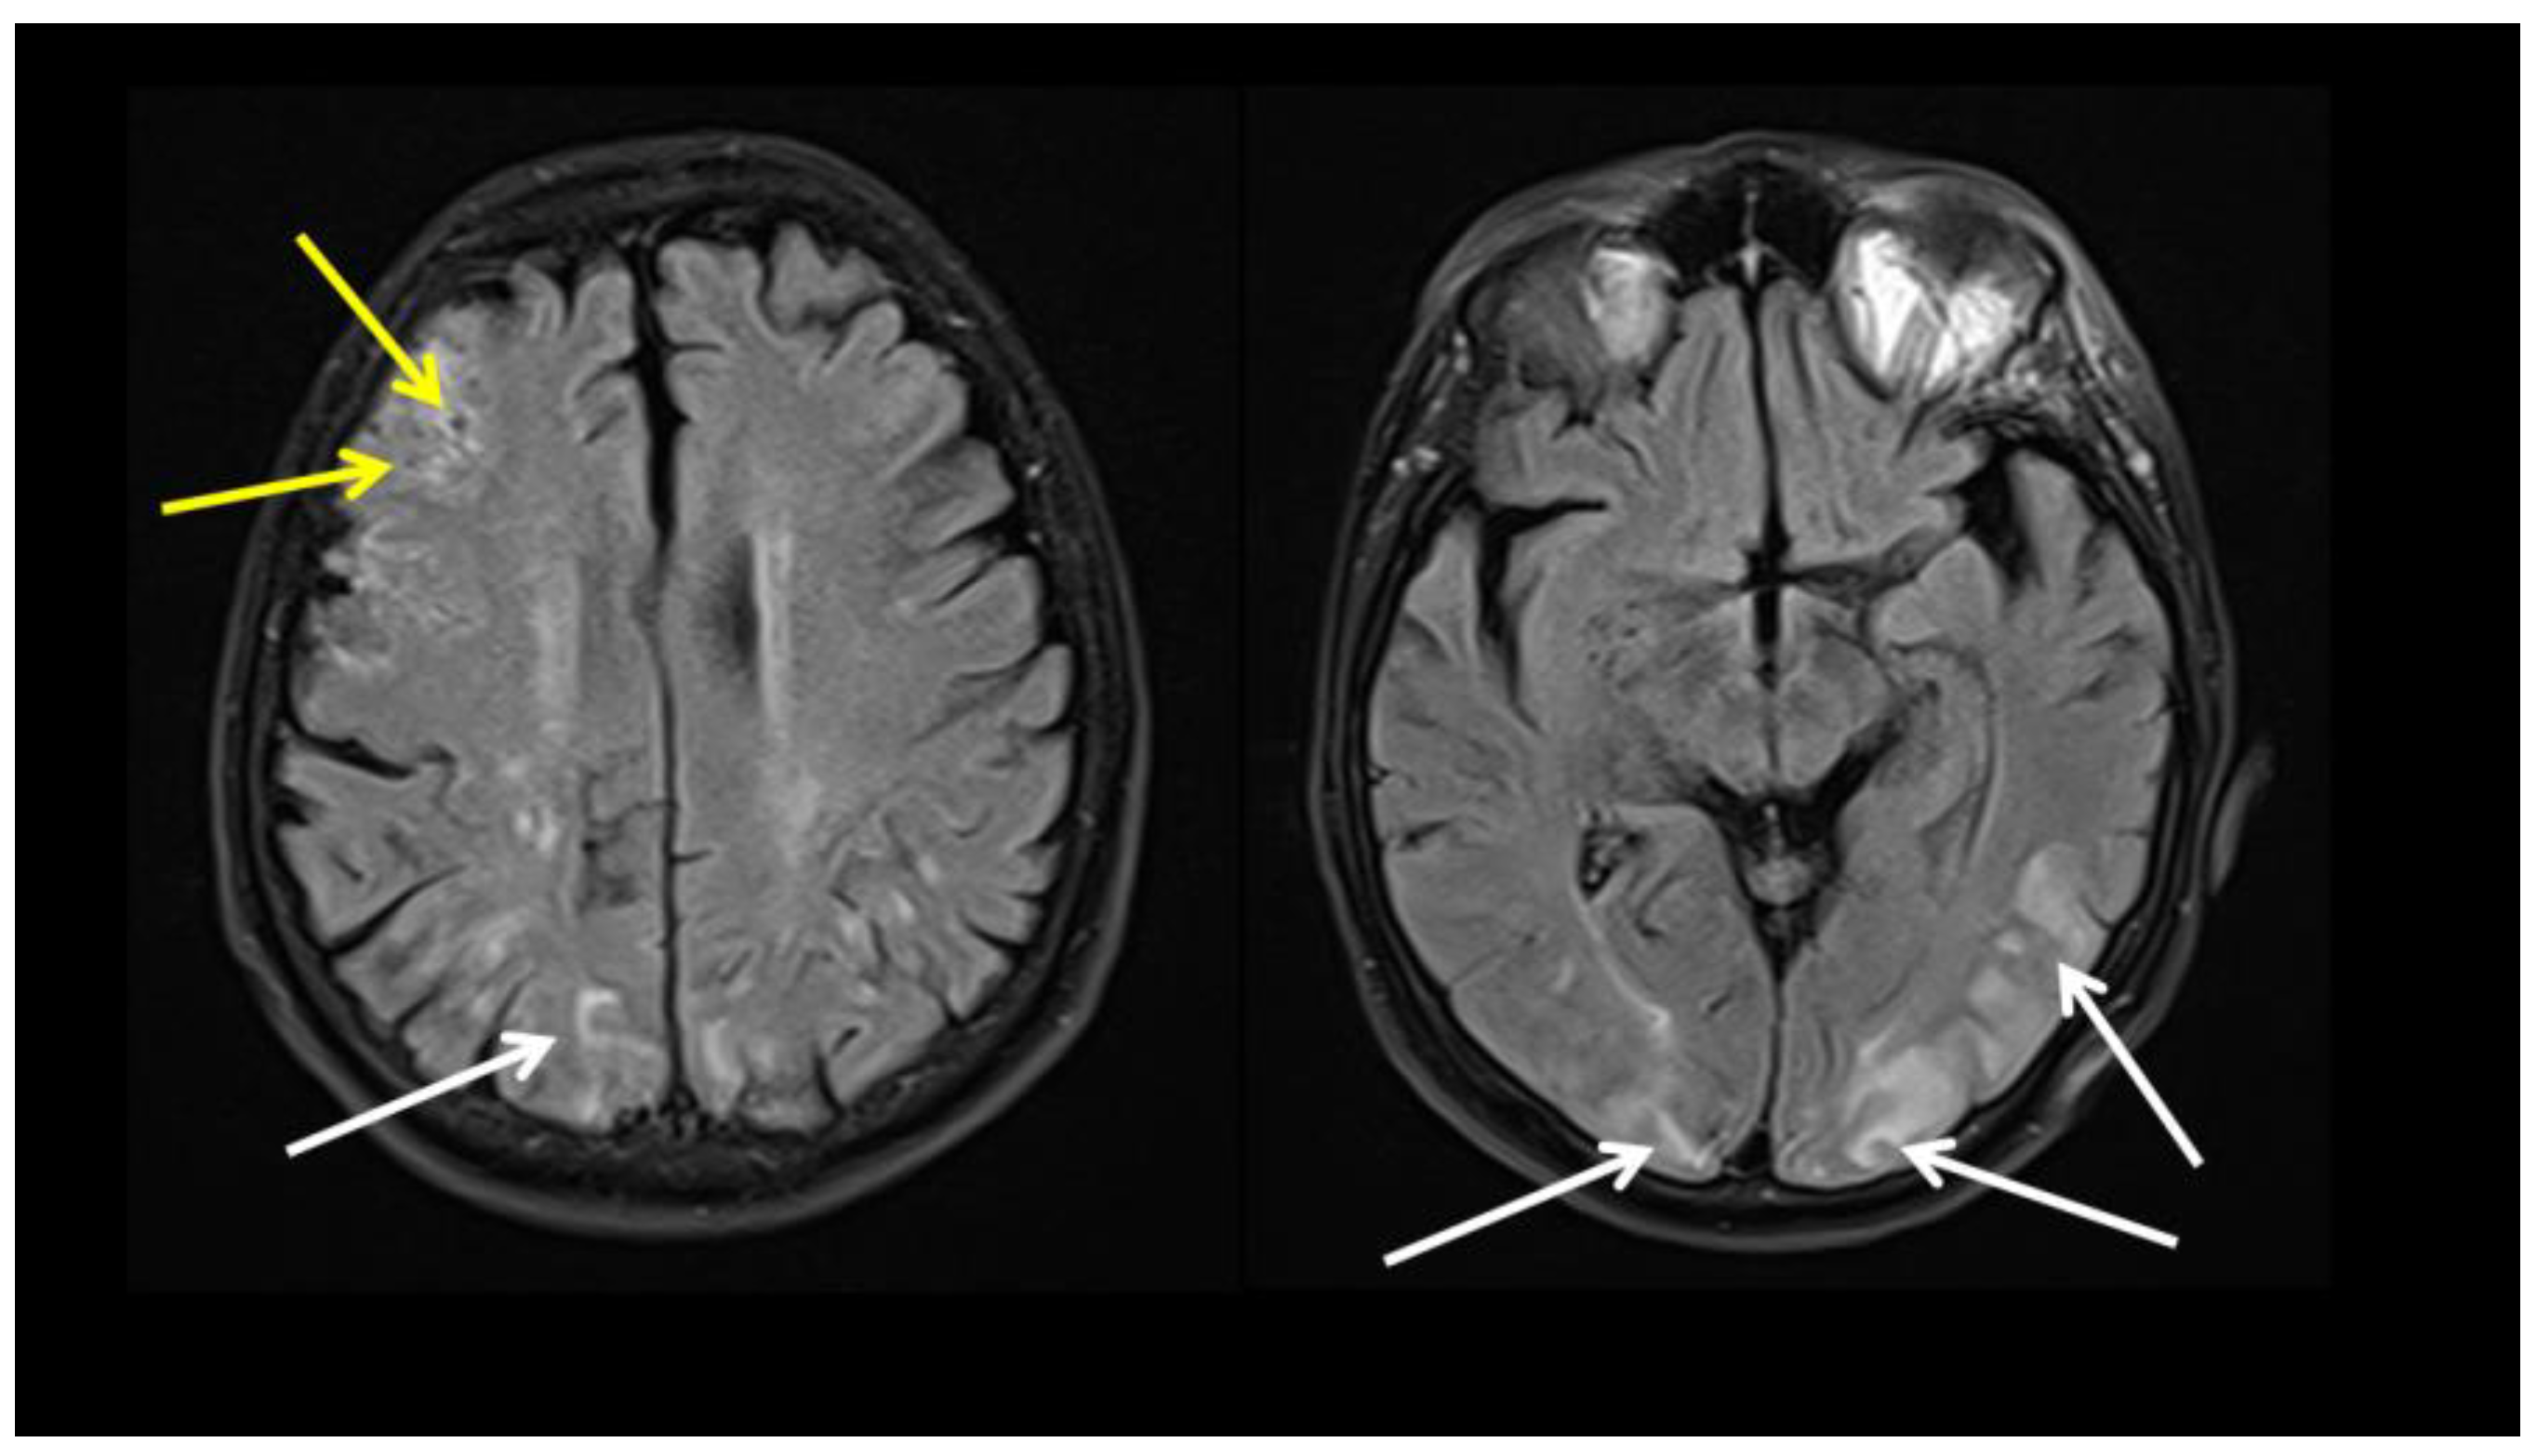

| Ivanovic J, et al., 2022 * [8] | 69 years, male | Headache, fever, elevated ESR, CRP, Fib, IL-6 | 6 weeks | LV-GCA Cerebral vasculitis | High dose CS, TPE Tocilizumab, IVIG, AZA | FDG PET CT Brain MRI | Improvement on treatment |